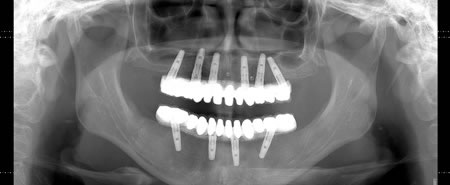

パノラマの最終補綴物セット後